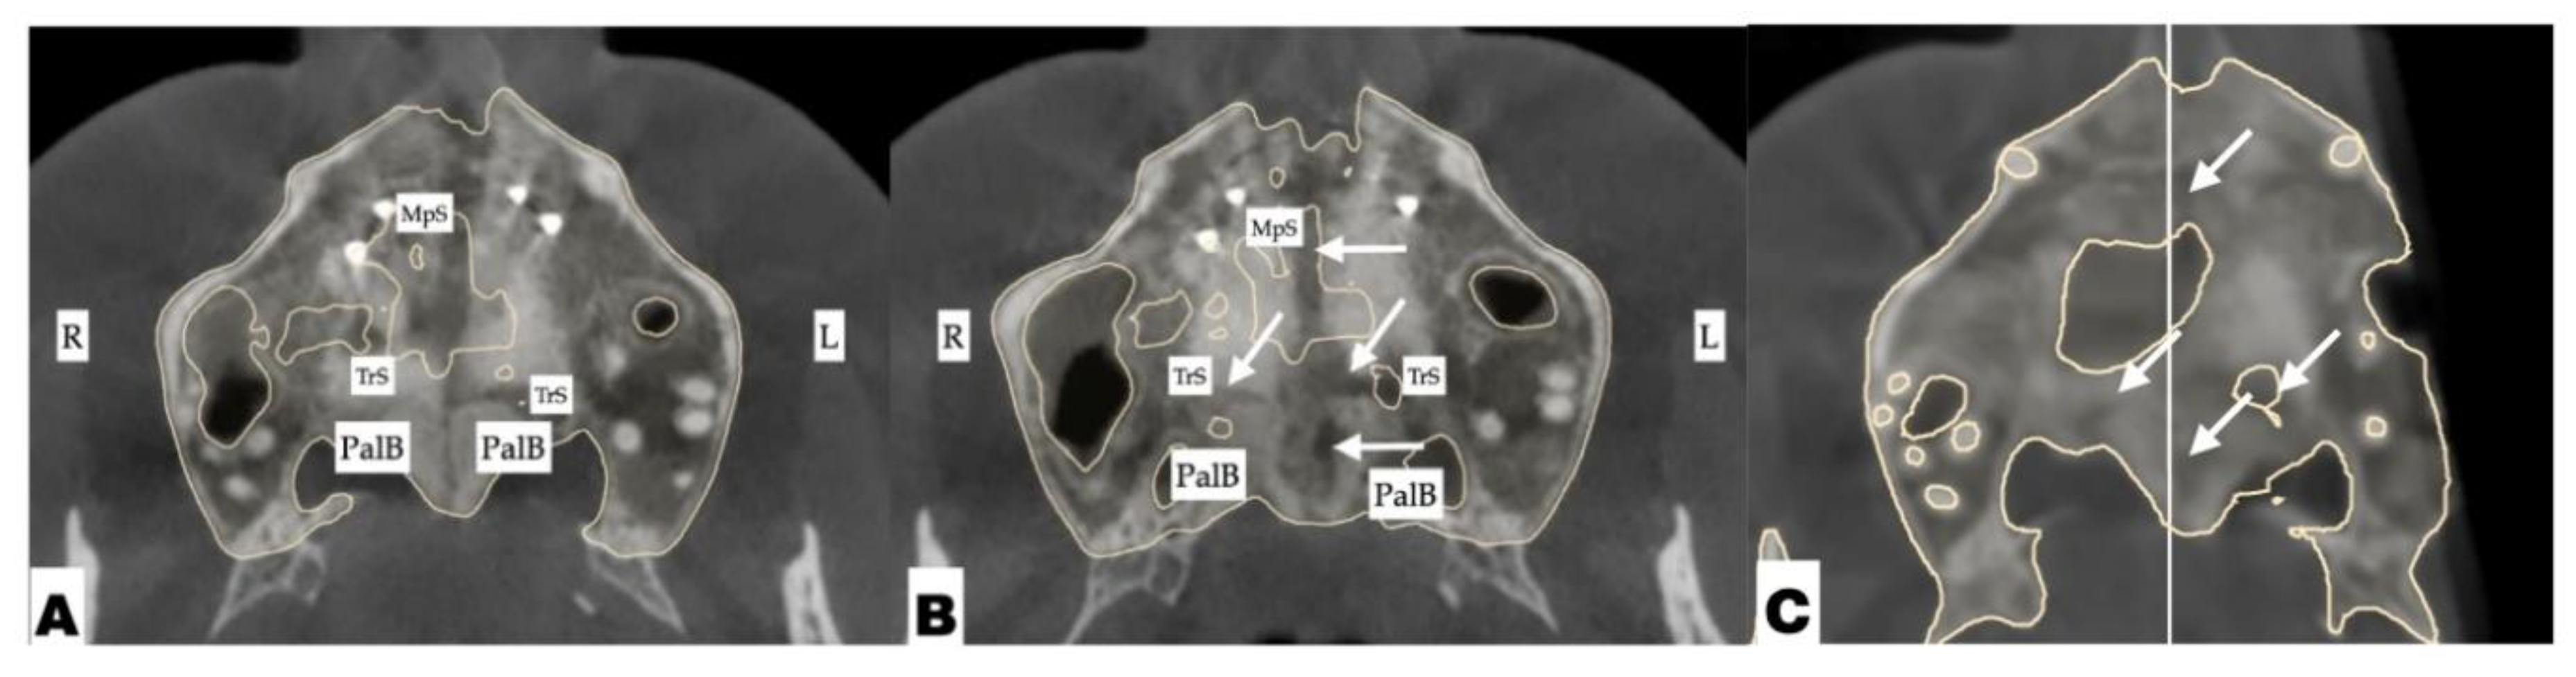

The expansion process lasted for 8 weeks with 1 turn/day, which translates to activation of approximately 0.11 mm/turn. The pattern of midpalatal suture separation was evaluated after the completion of expansion and is shown in Figure 12. The midpalatal suture was completely disarticulated, involving both the ANS and PNS areas. The transverse palatal suture showed signs of disarticulation as well, with the left side having a larger amount of separation.

Figure 12. Disarticulation of the midpalatal and transverse sutures with 3D-guided midpalatal piezocorticotomy-assisted MARPE expansion. Both axial slices show the disarticulation of the transverse suture with a greater degree of separation on the left side. Arrows point to areas of disarticulation. R—Right side; L—left side; MpS—midpalatal suture; TrS—transverse suture; PalB—palatine bone.